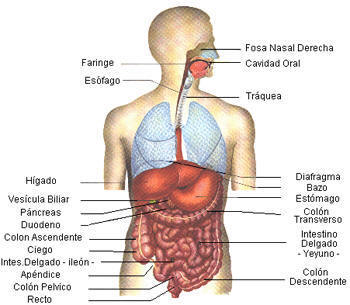

El aparato digestivo es un largo tubo, con importantes glándulas asociadas, siendo su función la transformación de las complejas moléculas de los alimentos en sustancias simples y fácilmente utilizables por el organismo.Estos compuestos nutritivos simples son absorbidos por las vellosidades intestinales, que tapizan el intestino delgado. Así pues, pasan a la sangre y nutren todas y cada una de las células del organismo

Esófago:Desde la boca hasta el ano, el tubo digestivo mide unos once metros de longitud. En la boca ya empieza propiamente la digestión. Los dientes trituran los alimentos y las secreciones de las glándulas salivales los humedecen e inician su descomposición química. Luego, el bolo alimenticio cruza la faringe, sigue por el esófago y llega al estómago, una bolsa muscular de litro y medio de capacidad, cuya mucosa secreta el potente jugo gástrico, en el estómago, el alimento es agitado hasta convertirse en una papilla llamada quimo.A la salida del estómago, el tubo digestivo se prolonga con el intestino delgado, de unos siete metros de largo, aunque muy replegado sobre sí mismo. En su primera porción o duodeno recibe secreciones de las glándulas intestinales, la bilis y los jugos del páncreas. Todas estas secreciones contienen una gran cantidad de enzimas que degradan los alimentos y los transforman en sustancias solubles simples.El tubo digestivo continua por el intestino grueso, de algo mas de metro y medio de longitud. Su porción final es el recto, que termina en el ano, por donde se evacuan al exterior los restos indigeribles de los alimentos.Descripción anatómicaEl tubo digestivo está formado por:

boca, esófago, estómago, intestino delgado que se divide en duodeno, yeyuno, íleon.

El intestino grueso. que se compone de: ciego y apéndice, colon y recto.

El hígado (con su vesícula biliar) y el páncreas forman parte del aparato digestivo, aunque no del tubo digestivo.

- El esófago es un conducto músculo membranoso que se extiende desde la faringe hasta el estómago. De los incisivos al cardias porción donde el esófago se continua con el estómago hay unos 40 cm. El esófago empieza en el cuello, atraviesa todo el tórax y pasa al abdomen a través del hiato esófagico del diafragma. Habitualmente es una cavidad virtual. (es decir que sus paredes se encuentran unidas y solo se abren cuando pasa el bolo alimenticio).

- Estómago:

- El estómago es un órgano que varia de forma según el estado de repleción (cantidad de contenido alimenticio presente en la cavidad gástrica) en que se halla, habitualmente tiene forma de J. Consta de varias partes que son : fundus, cuerpo, antro y píloro. Su borde menos extenso se denomina curvatura menor y la otra curvatura mayor. El cardias es el límite entre el esófago y el estómago y el píloro es el límite entre estómago y duodeno. En un individuo mide aproximadamente 25cm del cardias al pìloro y el diámetro transverso es de 12cm. Para ver cómo es el estómago por dentro pulsa aquí.

- Intestino delgado:

- El intestino delgado se inicia en el píloro y termina en la válvula ileoceal, por la que se une a la primera parte del intestino grueso. Su longitud es variable y su calibre disminuye progresivamente desde su origen hasta la válvula ileocecal. El duodeno, que forma parte del intestino delgado, mide unos 25 - 30 cm de longitud; el intestino delgado consta de una parte próxima o yeyuno y una distal o íleon; el limite entre las dos porciones no es muy aparente. El duodeno se une al yeyuno después de los 30cm a partir del píloro. El yeyuno-ìleon es una parte del intestino delgado que se caracteriza por presentar unos extremos relativamente fijos: El primero que se origina en el duodeno y el segundo se limita con la válvula ileocecal y primera porción del ciego. Su calibre disminuye lenta pero progresivamente en dirección al intestino grueso. El límite entre el yeyuno y el íleon no es apreciable. El intestino delgado presenta numerosas vellosidades intestinales que aumentan la superficie de absorción intestinal de los nutrientes.

- Intestino grueso:

- El intestino grueso. se inicia a partir de la válvula ileocecal en un fondo de saco denominado ciego de donde sale el apéndice vermiforme y termina en el recto. Desde el ciego al recto describe una serie de curvas, formando un marco en cuyo centro están las asas del yeyunoíleon. Su longitud es variable, entre 120 y 160 cm, y su calibre disminuye progresivamente, siendo la porción más estrecha la región donde se une con el recto o unión rectosigmoidea donde su diámetro no suele sobrepasar los 3 cm, mientras que el ciego es de 6 o 7 cm. Tras el ciego, la segunda porción del intestino grueso es denominada como colon ascendente con una longitud de 15cm, para dar origen a la tercera porción que es el colon transverso con una longitud media de 50cm, originándose una cuarta porción que es el colon descendente con 10cm de longitud. Por último se diferencia el colon sigmoideo, recto y ano. El recto es la parte terminal del tubo digestivo. Es la continuación del colon sigmoideo y termina abriéndose al exterior por el orificio anal.

- Páncreas:

- Es una glándula íntimamente relacionada con el duodeno, el conducto excretor del páncreas, que termina reunièndose con el colédoco a través de la ampolla de Vater, sus secreciones son de importancia en la digestión de los alimentos.

- Hígado:

- El hígado es la mayor víscera del cuerpo pesa 1500 gramos. Consta de dos lóbulos. Las vías biliares son las vías excretoras del hígado, por ellas la bilis es conducida al duodeno. normalmente salen dos conductos: derecho e izquierdo, que confluyen entre sí formando un conducto único. el conducto hepático, recibe un conducto más fino, el conducto cístico, que proviene de la vesícula biliar alojada en la cara visceral de hígado. De la reunión de los conductos cístico y el hepático se forma el colédoco, que desciende al duodeno, en la que desemboca junto con el conducto excretor del páncreas. La vesícula biliar es un reservorio musculomembranoso puesto en derivación sobre las vías biliares principales. Contiene unos 50-60 cm3 de bilis. Es de forma ovalada o ligeramente piriforme y su diámetro mayor es de unos 8 a 10 cm .